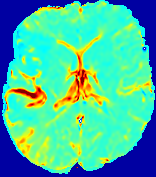

4.3.1 Advection Imaging via Advection-Diffusion

Slice #1Slice #2Slice #3Slice #4Slice #5Slice #6𝐕gt𝟐subscriptnormsuperscript𝐕gt2\|\bf{V}^{\text{gt}}\|_{2}Refer to captionRefer to captionRefer to captionRefer to captionRefer to captionRefer to caption𝐕est𝟐subscriptnormsuperscript𝐕est2\|\bf{V}^{\text{est}}\|_{2}Refer to captionRefer to captionRefer to captionRefer to captionRefer to captionRefer to captionRefer to caption1.51.51.51.21.21.20.90.90.90.60.60.60.30.30.30.00.00.0(mm/s)𝑚𝑚𝑠(mm/s)Destsuperscript𝐷estD^{\text{est}}Refer to captionRefer to captionRefer to captionRefer to captionRefer to captionRefer to captionRefer to caption0.0150.0150.0150.0120.0120.0120.0090.0090.0090.0060.0060.0060.0030.0030.0030.0000.0000.000(mm2/s)𝑚superscript𝑚2𝑠(mm^{2}/s)

Figure 14: PIANO identifiability testing: advection imaging via advection-diffusion. Top row shows 𝐕gt2subscriptnormsuperscript𝐕gt2\|{\bf{V}}^{\text{gt}}\|_{2} used for simulating ground truth pure advection. Rows below show the estimated 𝐕est2subscriptnormsuperscript𝐕est2\|{\bf{V}}^{\text{est}}\|_{2} and Destsuperscript𝐷estD^{\text{est}} on corresponding slices. Note that the plotted value scale for Destsuperscript𝐷estD^{\text{est}} is 0.01 of that for 𝐕gt2subscriptnormsuperscript𝐕gt2\|{\bf{V}}^{\text{gt}}\|_{2} and 𝐕est2subscriptnormsuperscript𝐕est2\|{\bf{V}}^{\text{est}}\|_{2}.

We use the same ‘Advection Imaging’ simulation of Sec. 4.2.1 as the concentration dataset for PIANO. However, instead of modeling pure advection (Eq. 15), we let PIANO estimate both velocity 𝐕estsuperscript𝐕est{\bf{V}}^{\text{est}} and diffusivity Destsuperscript𝐷estD^{\text{est}} via the advection-diffusion PDE (Eq. 2) underlying the proposed PIANO model. Fig. 14 shows the estimated 𝐕est2,subscriptnormsuperscript𝐕est2\|{\bf{V}}^{\text{est}}\|_{2}, and Destsuperscript𝐷estD^{\text{est}} fields for one patient. Although PIANO has the freedom to estimate both a velocity and a diffusivity field from pure advection, PIANO differentiates well between advection and diffusion: the estimated 𝐕est2subscriptnormsuperscript𝐕est2\|{\bf{V}}^{\text{est}}\|_{2} successfully reproduces the ground truth 𝐕gt2subscriptnormsuperscript𝐕gt2\|{\bf{V}}^{\text{gt}}\|_{2} governing the simulated advection process, just as it already did in the ‘Advection Imaging via Advection’ test (Fig. 12). More importantly, the estimated diffusivity Destsuperscript𝐷estD^{\text{est}} is orders of magnitudes smaller than 𝐕est2subscriptnormsuperscript𝐕est2\|{\bf{V}}^{\text{est}}\|_{2}, indicating the estimated diffusion is negligible compared to the estimated advection, which is highly consistent with the underlying pure advection of the simulated data.